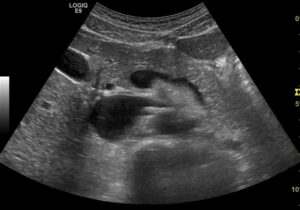

Cholezystolithiasis mit Cholezystitis